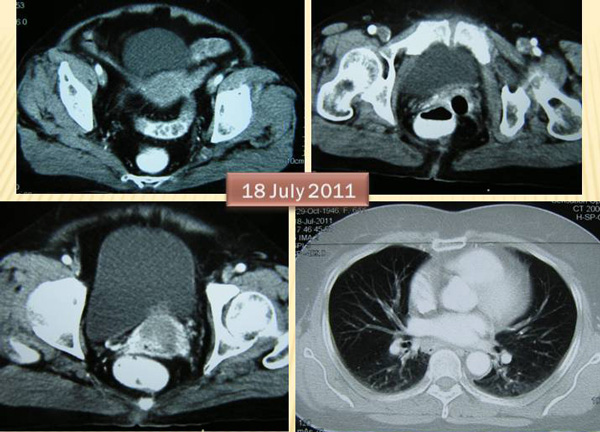

BH (S108) is a 65-year-old lady from Indonesia.  An ultrasound of her pelvis showed her cervix was enlarged with a focal bulge over the posterior part. This bulge or mass measures about 23 x 12 mm.

A chest X-ray on 13 July 2011 showed no significant abnormality see in the lungs and heart.

A biopsy was performed on 14 July 2011 and confirmed malignant cells infiltrating deep into the cervical parenchyma.  BH was referred to a cancer hospital for further management.

A CT scan was done on 18 July 2011. It showed a bulky uterine cervix measuring 4.9 x 3.7 cm with a hypodense lesion seen within.  This is in keeping with carcinoma of the cervix. No metastatic disease is evident in the abdomen.

BH underwent radiotherapy. She was told that there was a eighty-nine percent chance that she would be cured. BH had 25 sessions of external beam radiation and 3 sessions of brachytherapy (i.e. internal radiation).  In addition BH received 2 cycles of chemotherapy. All treatments were completed by 12 October 2011.